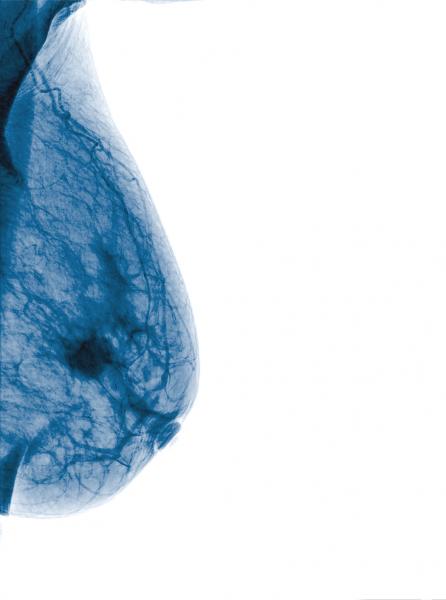

Despite decades of progress in breast imaging, one challenge continues to test even the most skilled radiologists ...

While mammograms play a vital role in efforts to identify breast cancer, they can present some challenges in women with dense breast tissue. Both dense breast tissue and cancer cells can appear as solid white in mammography, increasing the risk that results might be misinterpreted. Some recent advances in both technology and in communications about breast density have the potential to help clinicians and patients overcome these challenges in the years ahead.